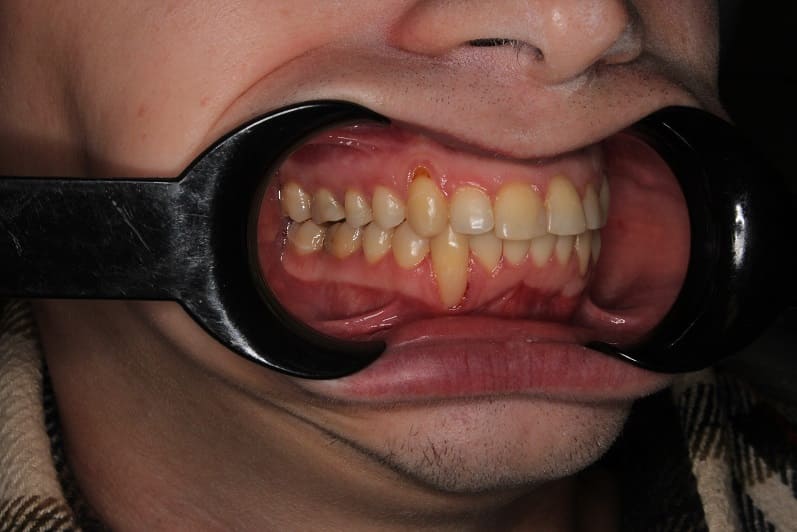

Ортодонтическое лечение на самолигирующейся брекет-системе

Ортодонтическое лечение на самолигирующейся брекет-системе заняло 2,5 года.